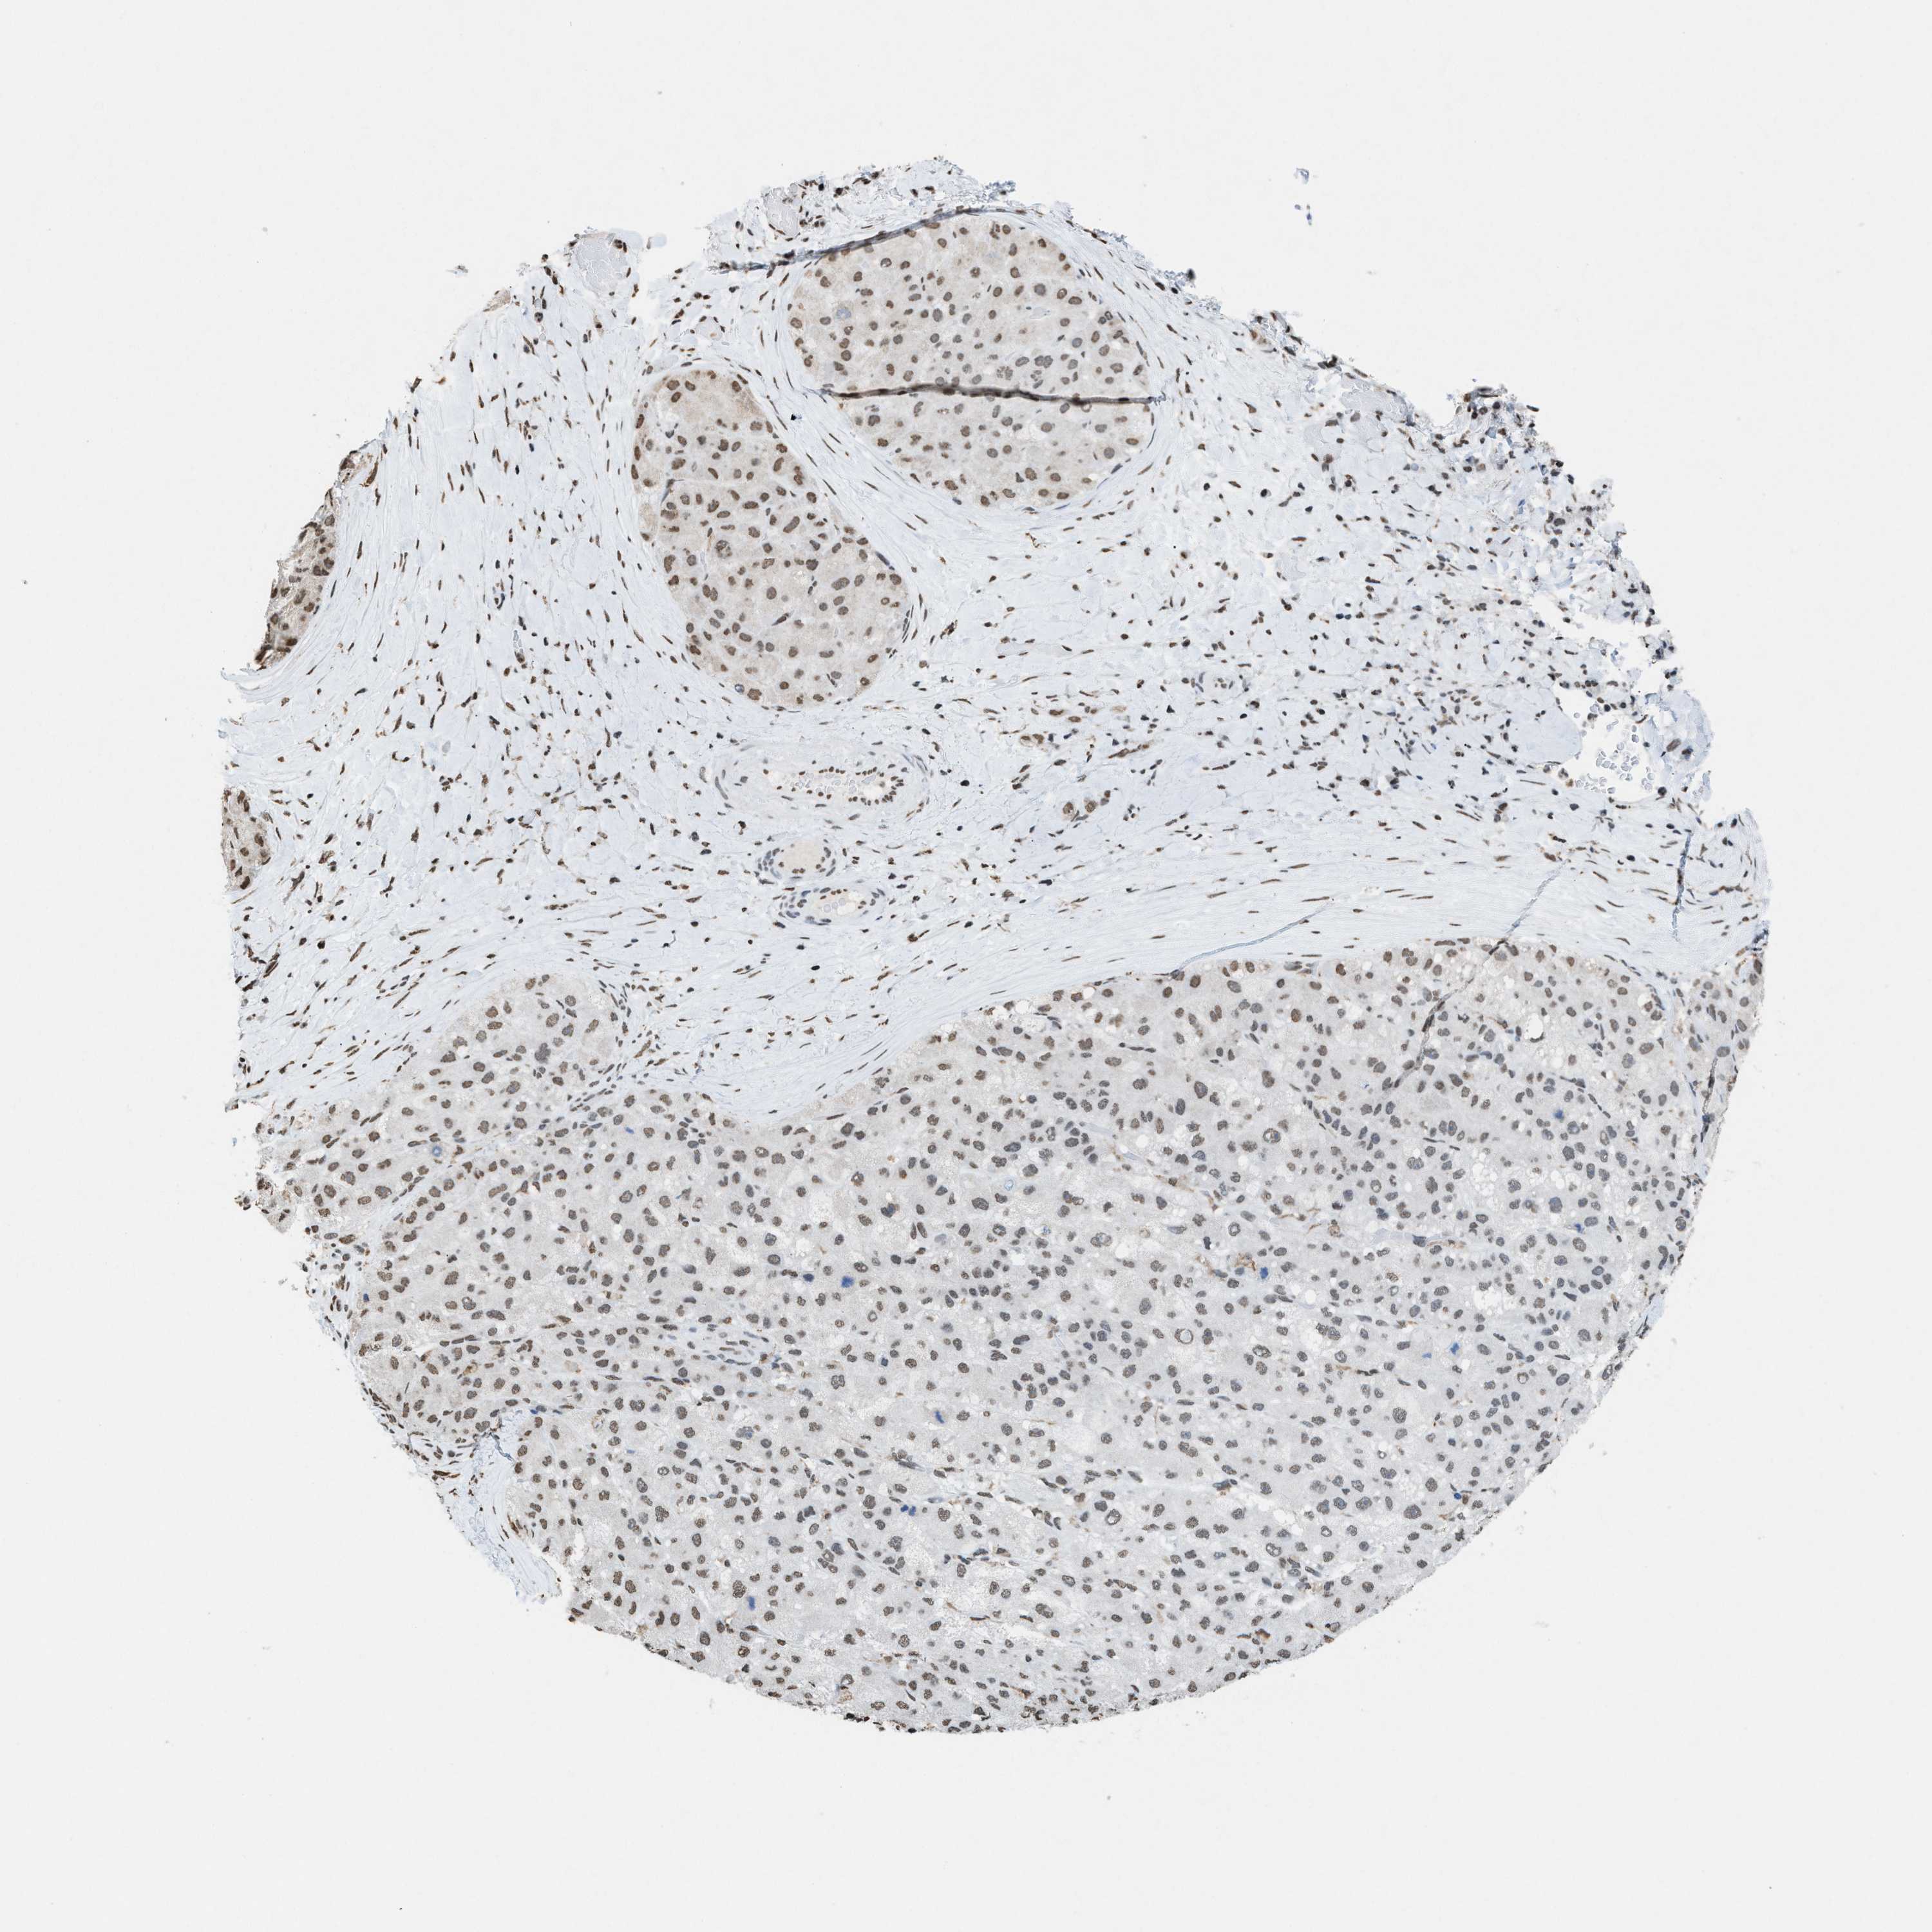

LIVER CANCER - Protein expressioni

A mouse-over function shows sample information and annotation data. Click on an image to view it in a full screen mode. Samples can be filtered based on level of antibody staining by selecting one or several of the following categories: high, medium, low and not detected. The assay and annotation is described here.

Note that samples used for immunohistochemistry by the Human Protein Atlas do not correspond to samples in the TCGA dataset.

Antibody stainingi

Antibody staining in the annotated cell types in the current human tissue is reported as not detected, low, medium, or high, based on conventional immunohistochemistry profiling in selected tissues. This score is based on the combination of the staining intensity and fraction of stained cells.

Each image is clickable and will lead to virtual microscopy that enables deeper exploration of all samples and also displays staining intensity scores, fraction scores and subcellular localization as well as patient and tissue information for each sample.

Antibody HPA021816

Antibody CAB002209

Staining

High

Medium

Low

Not detected

Intensity

Strong

Moderate

Weak

Negative

Quantity

>75%

75%-25%

<25%

None

Location

Nuclear

Cytoplasmic/membranous

Cytoplasmic/membranous,nuclear

Cholangiocarcinoma

Carcinoma, Hepatocellular, NOS